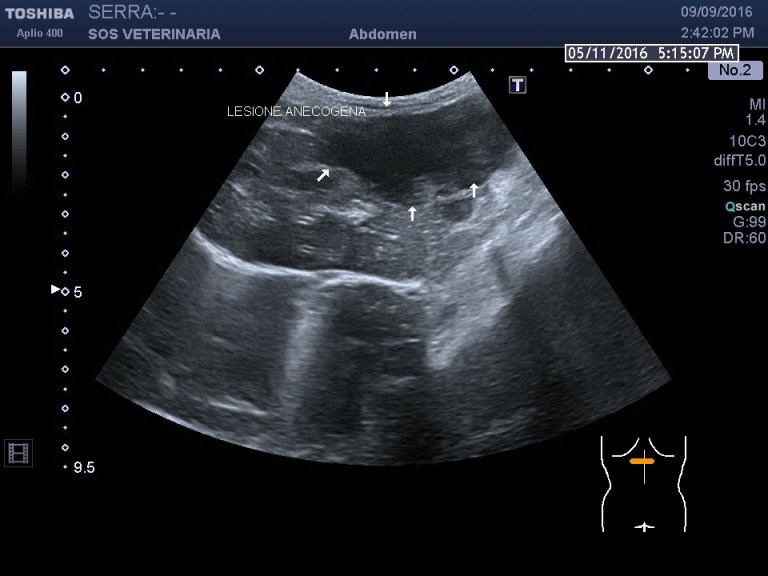

Gatta comune europea ,eta’ 5 anni ,improvvisa debolezza,vive in casa ,alla visita: mucose pallide,lieve distensione addome ,l’ecografia di base evidenzia emoperitoneo (versamento campionato) e due masse di alcuni centimetri ipoecogene peritoneali a profilo uniforme avascolari al color doppler , lesioni focali epatiche alcune molto demarcate ed ecogene altre consistenti in aree piu’ o meno demarcate con settori ane-ipoecogeni e settori ecogeni , demarcazione del profilo dei lobi nelle porzioni caudali meno definito.

sono evidenti lesioni focali avascolari (completa assenza di assunzione di contrasto) alcune non evidenziate all’esame B mode ,altre francamente ecogene in B mode ,lesioni dunque necrotiche demarcate purtroppo neoplastiche altamente suggestive di emangiosarcoma .